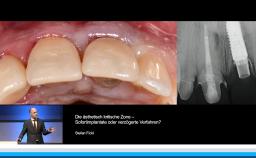

Basierend auf diversen Studien und eigener klinischer Erfahrung stellt Dieter Weingart seine Erkenntnisse und Schlussfolgerungen zum Thema Implantatverlust mit Defektbildung vor. Er illustriert das Thema mit eigenen klinischen Fällen inklusive Langzeit-follow-ups.